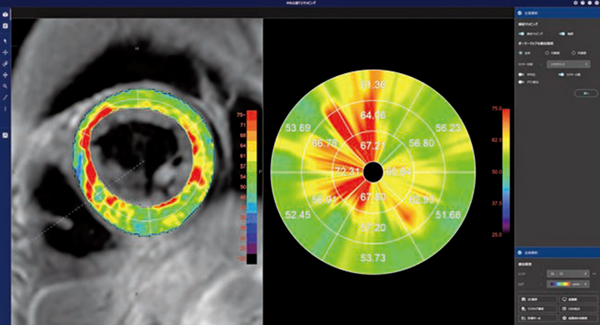

REVORASの「MR心筋T2マッピング」では,MR心筋T1マッピングと同様に,データを開くと同時に非剛体位置合わせやTE間のズレ補正が行われる。左室解析ステージでは,左室内腔と外壁の自動抽出を基にセグメントごとのT2値が評価できる。また,全体解析ステージでは,簡便に任意の領域のT2値計測による評価を行うことができる(図2)。

図2 MR心筋T2マッピング